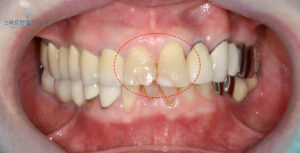

확인해보니,

오른쪽 위 앞니는 일부가 파절된 상태였으며

왼쪽 위 앞니는 예전에 시행한

레진의 색상이 자연치보다

훨씬 밝아 조화가 맞지 않았어요.

또한 레진과 치아 경계 부위에

미세한 파절이 생겨 틈이 보였는데,

이런 이유들로 인해 웃을 때마다

심미적으로 큰 불편감을 느끼셨답니다.